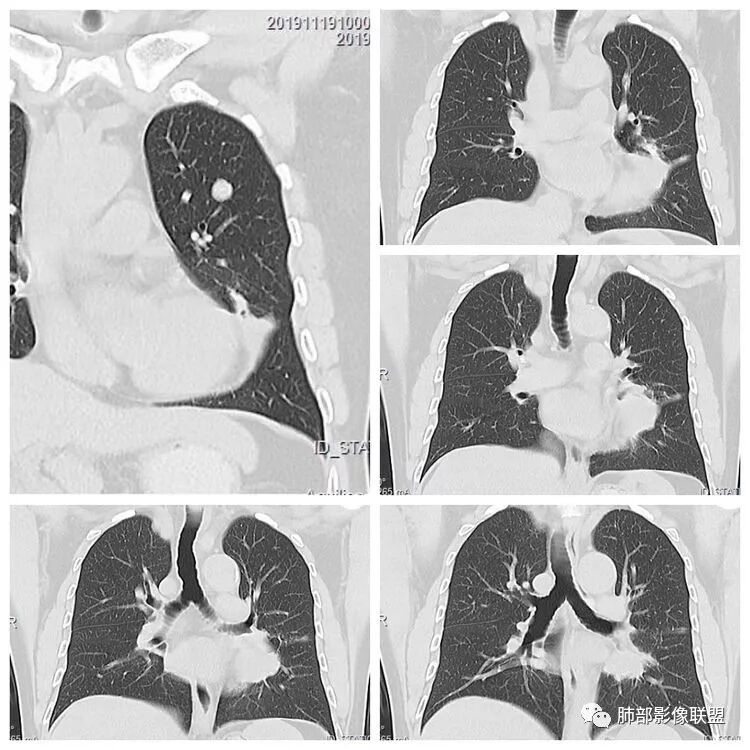

3.左肺上叶另见孤立结节影,边界清楚光整,中央钙化,未见脂质密度特征。

左肺上叶孤立小结节影未见异常强化。

7.左肺上叶孤立小结节影中央钙化可见于肠道肿瘤,但更多见于错构瘤,或是结核球。

左上肺光滑圆形结节,内有钙化,密度不均,错构瘤;

3.至于那个结节。是否一元不太好说。给的不是薄层似乎,强化没有说。目测是一个比较光滑的病变,有微分叶。那套路就是判断与支气管血管关系看看。血管关系很重要,错构瘤是推移,psp是贴边,转移应该会有血供,血管会增粗,这个需要细节。孤立结节疾病谱有错构瘤,psp,肺本身另外一个肺癌,转移,结核球。也可以从这个病灶入手

初学者:这个结节里面点状高密度究竟是血管还是钙化,视频看不清楚,大家可以讨论一下。很有帮助下面这个图可以看到病灶整体有彭隆以及强化不均血管如果给我重建一下就好了,如中央钙化,强化弱,又血管推移,边缘这么光滑的又钙化,一般概率上良性的错构瘤最多,转移保险起见要排一排。